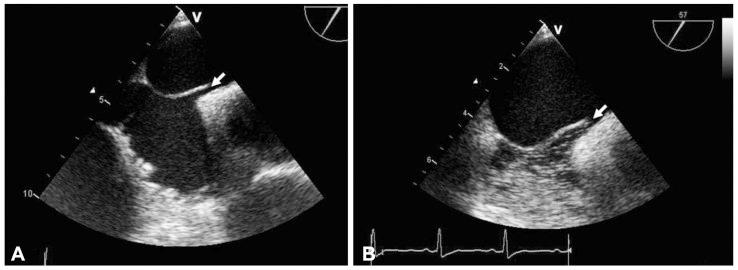

A case of cryptogenic stroke associated with patent foramen ovale coexisting with pulmonary embolisms, deep vein thromboses, and renal artery infarctions.

A paradoxical embolism is defined as a systemic arterial embolism requiring the passage of a venous thrombus into the arterial circulatory system through a right-to-left shunt, and is commonly related to patent foramen ovale (PFO). However, coexisting pulmonary embolisms, deep vein thromboses (DVT), and multipe systemic arterial embolisms, associated with PFO, are rare. Here, we report a patient who had a cryptogenic ischemic stroke, associated with PFO, which is complicated with a massive pulmonary thromboembolism, DVT, and renal infarctions, and subsequently, the patient was treated using a thrombolytic therapy.

矛盾性栓塞定义为静脉血栓通过右向左分流进入体循环动脉系统导致的全身性动脉栓塞,通常与卵圆孔未闭(PFO)有关。然而,PFO 并发肺栓塞、深静脉血栓形成(DVT)和多发性体循环动脉栓塞较为罕见。在此,我们报告了一例伴有 PFO 的隐源性缺血性脑卒中患者,该患者并发了巨大的肺血栓栓塞、DVT 和肾梗死,随后接受溶栓治疗。